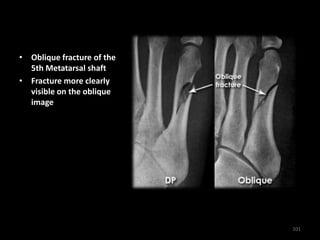

• Oblique fracture of the

5th Metatarsal shaft

• Fracture more clearly

visible on the oblique

image

101